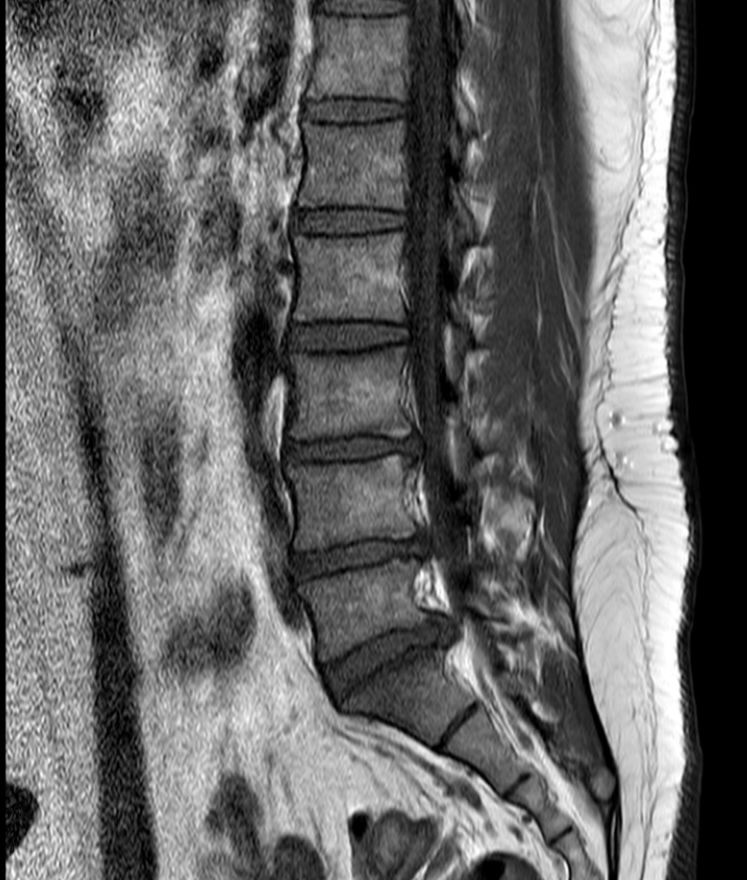

아래 첨부한 사진이 제 MRI 사진인데 집에서 요가매트로 간단하게 할만한 스트레칭 자세 추천해주실수있을까요?